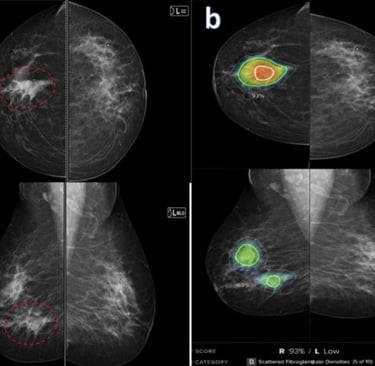

This growing popularity of AI in medicine has also raised many concerns within the medical industry, particularly in the field of medical screening. Given its efficiency and potential to advance image acquisition, medical imaging is a field that has been using AI extensively. According to an article titled Redefining Radiology: A Review of Artificial Intelligence Integration in Medical Imaging, published under the National Institute of Health (NIH), AI has technically been used pretty early on in the field of medical screening through computer aided detection (CAD) since its approval by the FDA in 1998. CAD is an advanced software that helps doctors identify potential abnormalities in mammography screenings. By improving disease detection, image segmentation, and streamlined workflows, AI integration in CAD makes cancer and disease detection more efficient.

“There are different ways that we try to address this and one of them is integrating something called ‘explainable AI.’ This tells us how the AI system came up with the interpretation that it did. But you're right, it is very hard for a breast imager to believe ai when they don't know how it came up with that interpretation. If there is a density on the mammogram, and that AI flags this density as suspicious, a radiologist may say it does not look suspicious and dismiss the finding. However, if the radiologist knew that AI came up with this density as being suspicious because there is an irregular margin and it points to where that margin is, the radiologist is more likely to believe and accept this interpretation.”